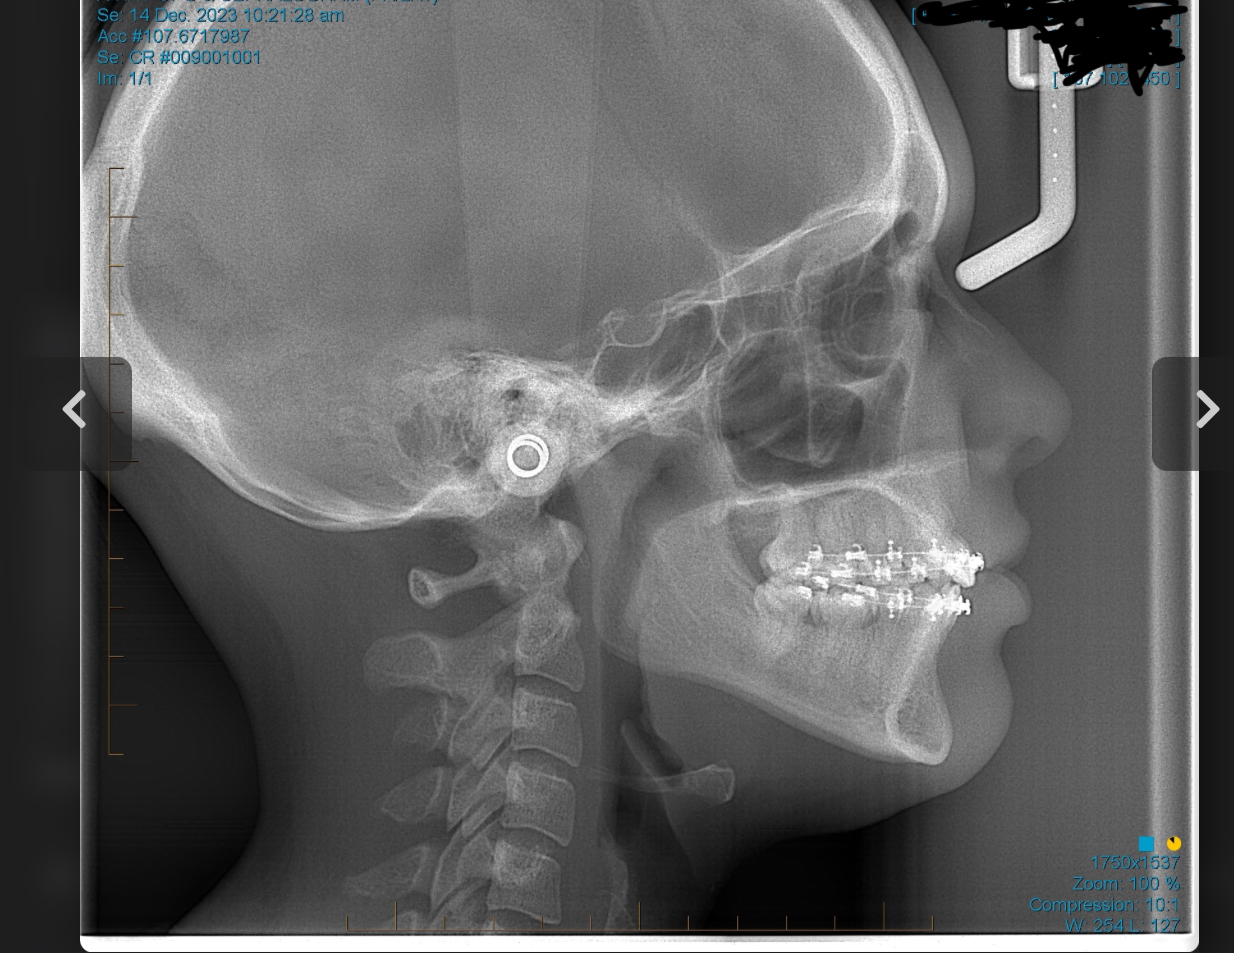

sfs, no ramus and zygos, retrusive, low hyoid, crossbite, crooked/slanted and retracted maxilla, mandible asymmetry, right side of face grown more than left, 8 extractions at 13 (including premolars).